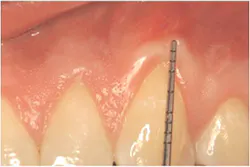

Thirdly, measure the clinical probing depth (pocket depth to the sulcus) (see Figure 4). To calculate the attached gingiva, subtract the probing depth from the outside measurement of the gingiva for the total width of of attached gingiva. Record the width of the attached gingiva and identify any teeth that need tissue regeneration, such as root coverage surgery (see Miller classification I-III, Table 1).